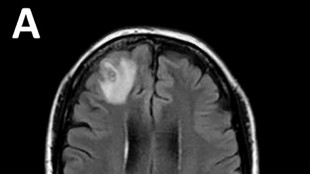

Vacuna contra cáncer de piel podría estar disponible en 2025, dice director ejecutivo de Moderna

El director general de Moderna, Stéphane Bancel, dijo a la AFP que la vacuna experimental contra el melanoma que elaboró su compañía podría estar disponible en tan solo dos años, lo que supondría un paso histórico contra la forma más grave de cáncer de piel.